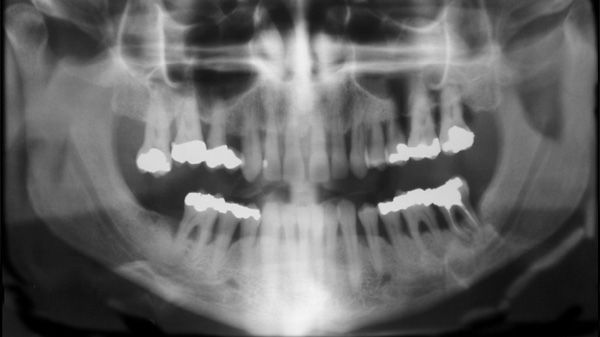

​Kan tandlossning och ledgångsreumatism hänga ihop?

Finns det en koppling mellan parodontit och reumatoid artrit? Det vill säga mellan tandlossning och ledgångsreumatism. Det vill en grupp forskare ta reda på och får nu drygt 700 000 kr till sitt förfogande av Eklund Foundation.

Stefan Renverts projekt får närmare hälften av stiftelsens avsatta medel för 2016 till sitt forskningsprojekt. Tio procent av världens vuxna befolkning lider av en allvarlig form av paradontit, alltså tandlossning, vilket gör den till den sjätte vanligaste sjukdomen i världen. Parodontit initieras av mikroorganismer men är liksom reumatoid artrit (RA, eller ledgångsreumatism) en inflammatoriskt driven sjukdom. Sjukdomarna delar många riskfaktorer, som exempelvis rökning, och har genetiska kopplingar i att patienten bryter ner vävnad, inflammationsceller medverkar i den aktiva sjukdomen och symtomen påverkas av anti-inflammatorisk behandling.